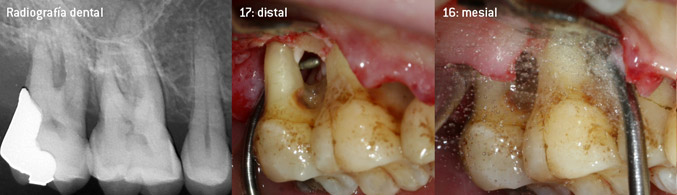

Como precursores del desarrollo de la nueva punta diamantada 3AP para eliminadores de sarro neumáticos, los dos odontólogos constataron que era necesario limitar el uso de las puntas diamantadas que se estaban comercializando hasta la fecha, sobre todo durante los tratamientos de furcaciones o en bolsas interradiculares estrechas. Además, esto debe llevarse a la práctica independientemente de si se trata de un procedimiento no quirúrgico (figura 2) o de un procedimiento quirúrgico (figura 3).

Desbridamiento abierto de las furcaciones de las piezas 16 y 17

Fig. 3: Desbridamiento abierto de las furcaciones de las piezas 16 y 17 con pérdida de adherencia avanzada